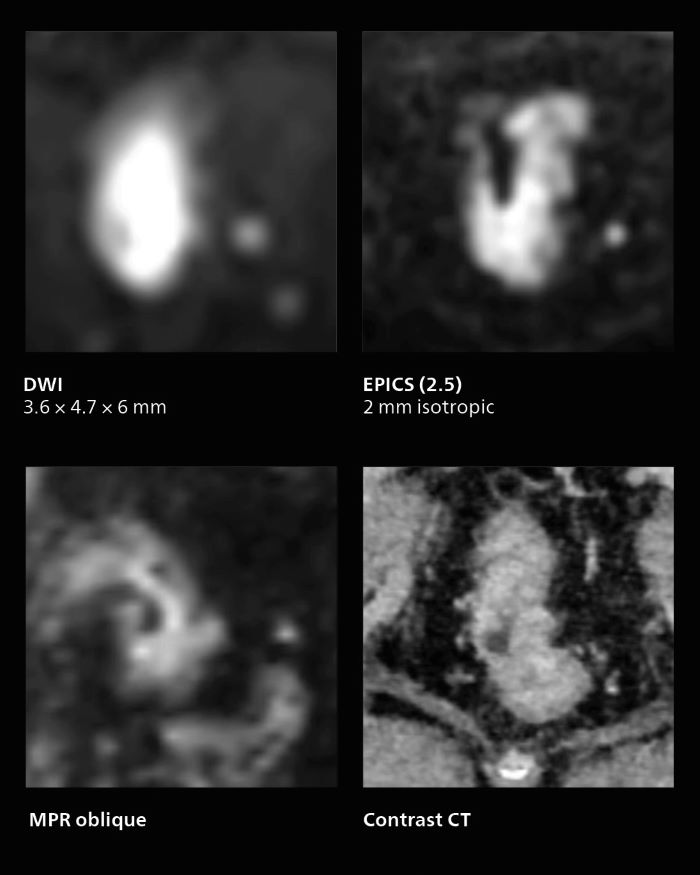

MRI of rectal cancer

In this patient MRI was done to help in diagnosing the depth of invasion. Performed on Elition X.

Notable improvement in diffusion-weighted imaging

With SmartSpeed, Kumamoto Chuo Hospital also has the ability to use EPI diffusion-weighted imaging (EPICS-DWI) with Compressed SENSE, which is an important step forward according to Dr. Katahira. “Before, our EPI diffusion was performed using SENSE, but now with Compressed SENSE it is possible to obtain very clear images,” he says. He also describes the benefit of being able to perform 3D diffusion-weighted imaging. “Previously, we only had DWI images in one direction to make a diagnosis. Now, we can do something that was not possible before: performing a DWI volume acquisition so that multiplanar reconstruction can be used, allowing us to look at scan results from all directions to make the diagnosis,” Dr. Katahira says. “What used to be a diagnosis based on just cross-sectional images, can now be based on a volume image. This is a dramatic improvement for us, because it is now possible to look at slices in various cross section directions. For example, the presence or absence of venous invasion is very important in rectal cancer patients, because venous invasion can cause metastasis in the future. The ability to reconstruct images according to the direction of the blood vessels, allows us to see venous infiltration more realistically, which is a world of difference from what we were used to.”